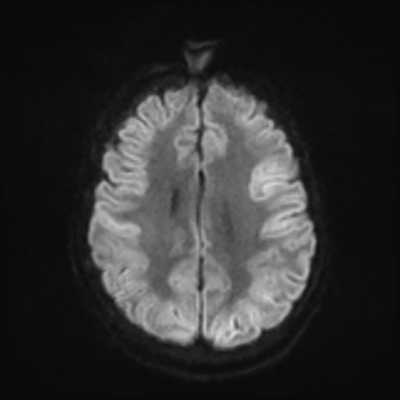

MRI brain (DWI)

MRI brain (DWI) 4/24 4/24

You can clearly see diffuse cortical and basal ganglia diffusion restriction, and that of his deep cerebellar nuclei as well. The right occipital lobe abnormalities are a little more prominent, but then you remember that he is known to have had a right occipital stroke weeks ago.

In reviewing his data, you know that he doesn't have any of the strong predictors of a poor neurologic prognosis. However, based on these findings on MRI, along with the absent reactivity on cEEG, you are able to tell the primary team and the patient's family that he is likely to have a poor prognosis, based on these multiple moderate predictors. Recovery is not completely impossible-- there is more uncertainty with this prognostication than if we were able to get SSEPs-- but you're very worried about his outlook and that any potential recovery would require a very protracted rehabilitation period. Given his high cervical cord injury level, tracheostomy would be required anyway. So, it comes down to whether his family thinks he'd want to pursue these aggressive measures.